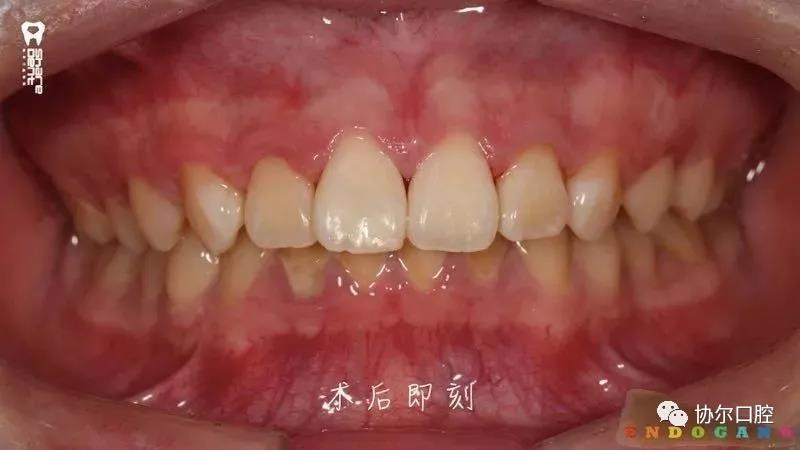

好多朋友都在问有没有前牙外伤折断后美塑树脂断牙显微再接的病例,正当小编“愁眉苦展”时,喻刚老师雪中送炭来了。15岁青少年断牙24小时,破镜重圆,修旧如旧。

首先美塑树脂具有可以反复加热的特性,当把充填用的膏体树脂用专用的加热器加热至55℃时,树脂流动性增强,其流动性比一般的流体树脂略弱,接近于某些高填料的流体树脂,非常适合粘接操作。其次,膏体树脂填料含量比流体树脂高,粘接后的一些表现比普通流体树脂更好,比如耐磨强度。第三,充填树脂没有像双固化粘接树脂的自固化功能,所以留给医生的操作时间非常充分,医生可以反复检查粘接边缘的对位和仔细清除多余的粘接树脂。第四,使用美塑牙本质树脂进行断牙粘接还可根据牙体颜色进行多达9种颜色的牙本质树脂的颜色选择及匹配。

基于以上四点,使用美塑树脂进行断牙粘接是一种较好的选择和推荐。显微技术的运用进一步增加了断牙再接的精准度和精细度,为更多更长久保存天然牙以及折断的牙体组织,断牙显微再接技术值得选择和推广。